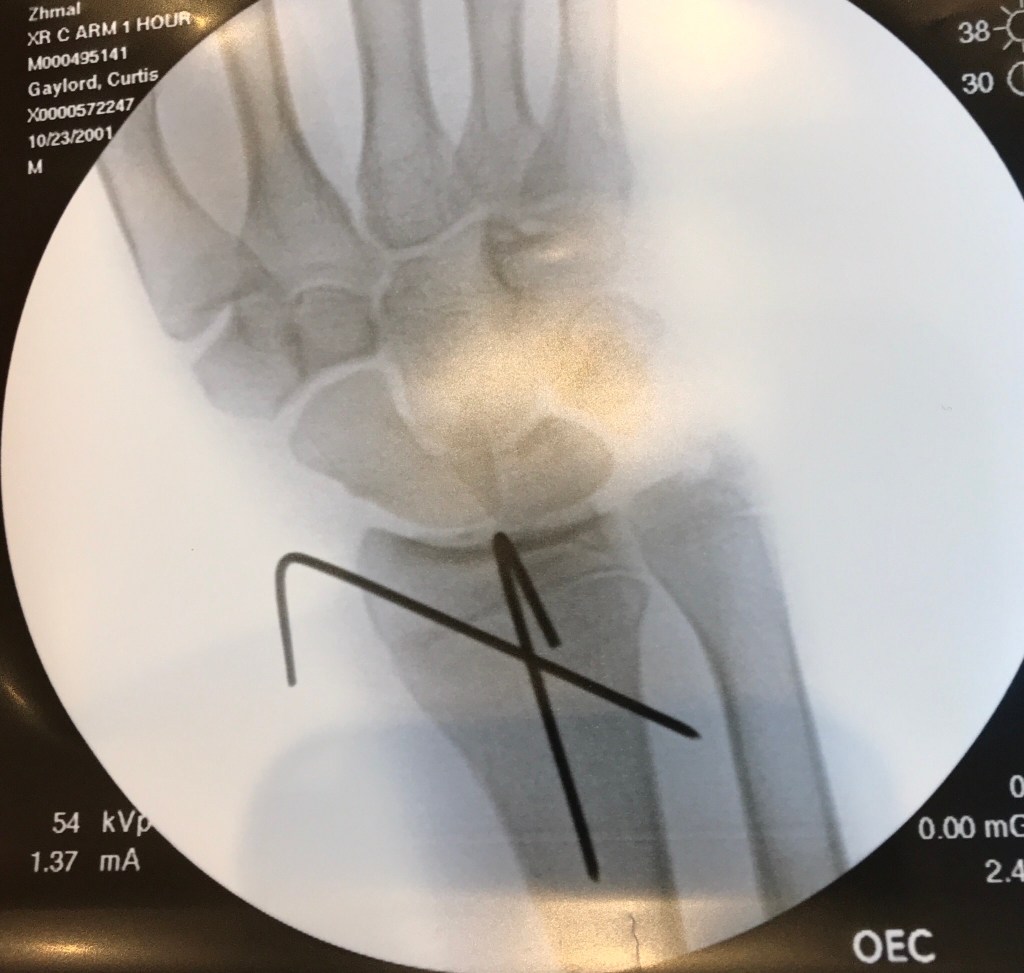

So we went to the doctor on Tuesday and by Wednesday morning he was getting it fixed. The fix required two pins to be placed in his wrist for the next few weeks and then they will be removed and he will be in a cast for a few more weeks. No physical therapy should be required, though it will take a bit for him to get his muscle tone back after not using his wrist for 2 months.